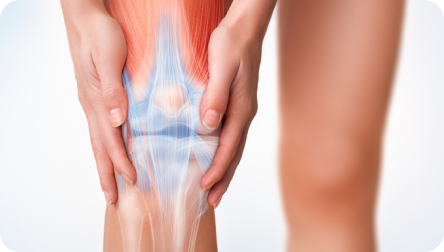

La rodilla es una articulación compleja. Es la más grande del esqueleto y la encargada de recibir el peso del cuerpo cada vez que una persona salta o cae. Como tal, puede realizar los movimientos de flexión-extensión y rotación sobre el eje longitudinal de la pierna cuando la rodilla esté flexionada. Por medio de la rodilla se unen el extremo inferior del fémur, el extremo superior de la tibia y la rótula.

Además de los componentes óseos, la rodilla presenta estructuras blandas que participan activamente en la movilidad y estabilidad de esta articulación. Las más importantes -y que mayormente se lesionan- son los meniscos y los ligamentos.